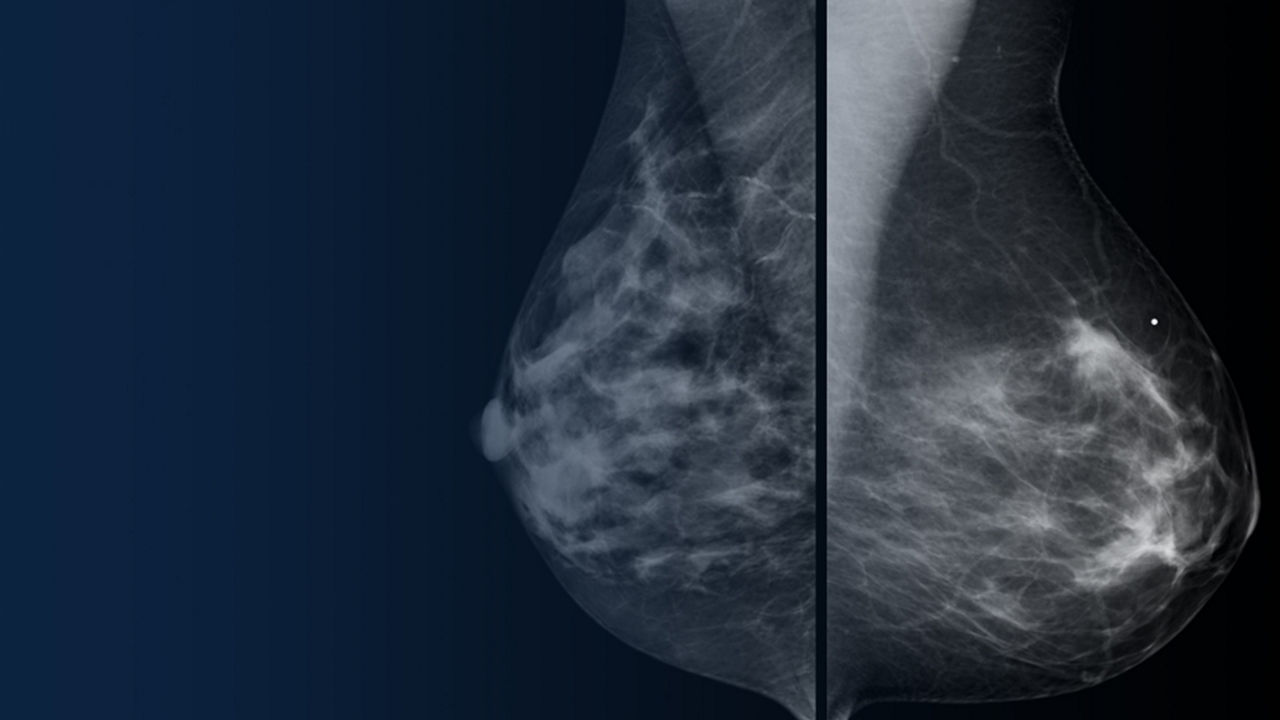

Leveraging transformational imaging technology to realize the promise of precision medicine and help deliver better outcomes. Our medical imaging products range from systems, including MRI, CT, PET, SPECT, Ultrasound, Mammography and X-ray, to digital and AI solutions to help drive healthcare digitialization, help enable faster exam workflow, improve clinical outcomes and increase efficiencies.